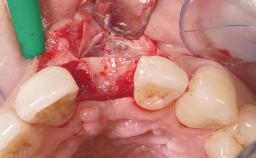

A 39-year-old male patient presented with a chief complaint of discomfort and gingival discoloration around his maxillary left central incisor. He was in good general health and was a non-smoker. His past dental history was significant because of the traumatic fracture of tooth 21 in a sporting accident at age 13. Initial dental treatment included endodontic therapy and a full-coverage restoration. The patient became symptomatic 5 years later, when structural failure of the tooth resulted in the dislodgment of the crown. Endodontic retreatment, apical surgery, and post-and-core restoration were performed.

| Bone Augmentation | Horizontal|Staged |

| Soft Tissue Grafting | Simultaneous |